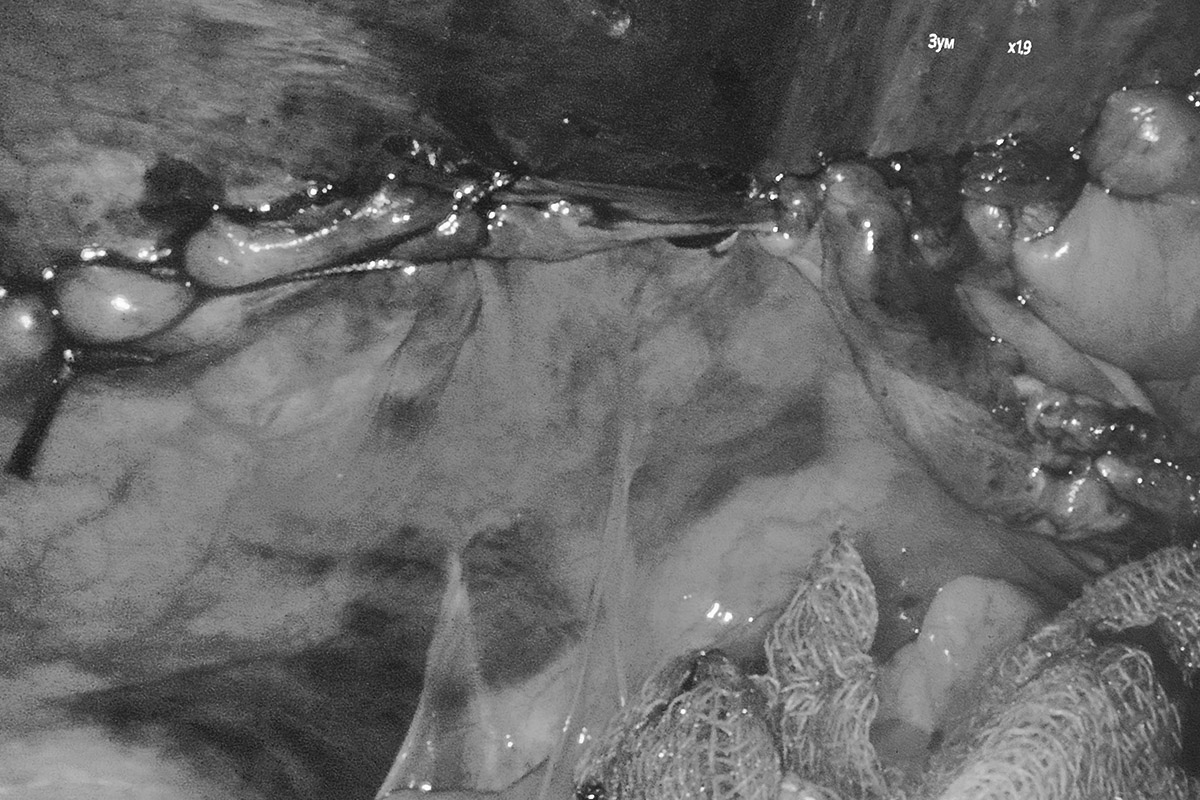

Открытая операция по поводу паховой грыжи предусматривает хирургический доступ к грыжевому мешку. Врач осторожно выделяет его, возвращает содержимое в брюшную полость или удаляет при больших грыжах. Далее в паховый канал устанавливается синтетическая сетка-трансплантат, после чего рану ушивают.

Метод Лихтенштейна — это классическая операция на паховой грыже по укреплению задней стенки пахового канала с использованием синтетической сетки. Сетка интегрируется в ткани организма, снижая риск повторного образования грыжи до 1%. Метод эффективен для крупных грыж и сопровождается минимальной болью и коротким восстановительным периодом. Этот способ широко используется благодаря своей надёжности.

- Операция Лихтенштейна: Через небольшой разрез устанавливается сетка, укрепляющая паховый канал. Это надёжный метод с минимальным риском рецидивов, реабилитация также занимает несколько дней.